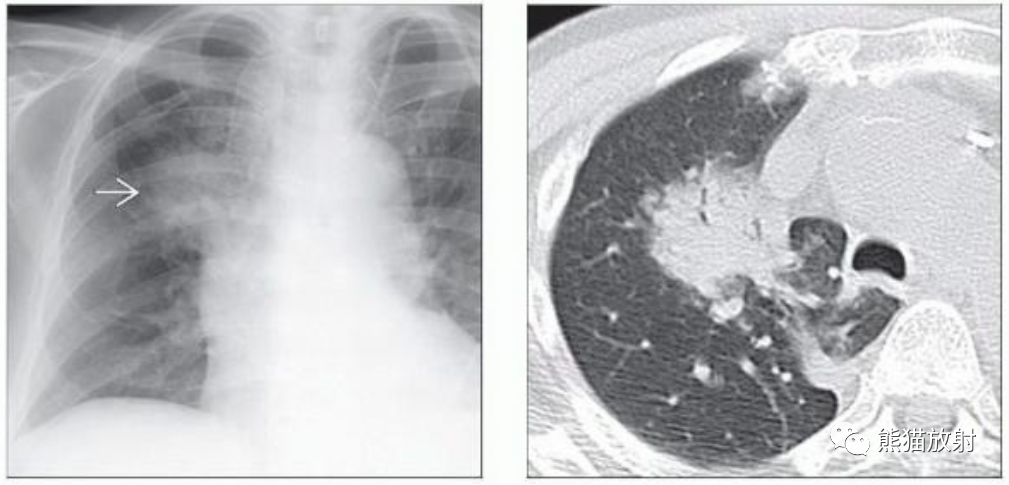

(左) 40岁男性,慢性右上叶肺结核病史,轴位CECT显示霉菌球,表现为腔内后部一部分钙化的结节。

(右)同一患者,俯卧CECT显示腔内霉菌球移动至重力依赖部位。在俯卧位重复低剂量 CT 有助于显示疑似霉菌球的腔内活动性。